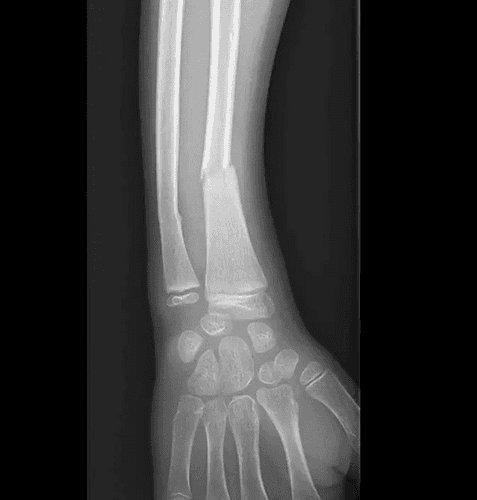

Suivi évolutif de consolidation d'une fracture du radius chez l'enfant

RX